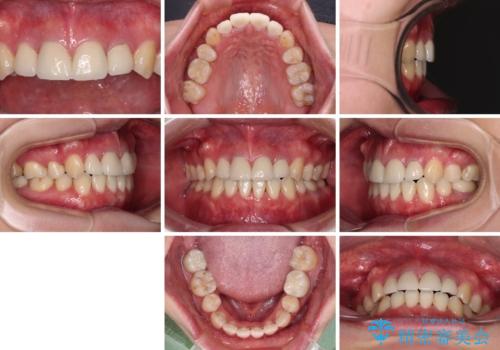

- 治療期間

- 2年8ヶ月

開咬の改善には舌突出癖を改善するためのトレーニングが必要ですが、しっかりと行っていただき、想定よりも早い期間で治療を終えることができました。